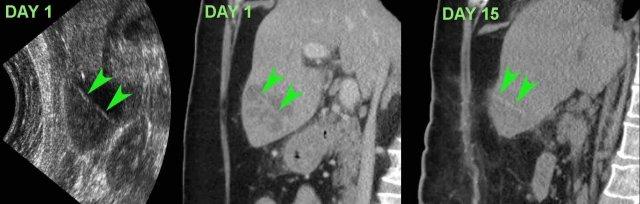

Bệnh nhân này nhập viện với đau bụng trên và CRP 245. Siêu âm và CT phát hiện một dị vật thẳng, hơi tăng tỷ trọng, có thể là tăm cocktail (đầu mũi tên).

Trong phẫu thuật hai ngày sau, áp xe gan đã được dẫn lưu, nhưng không tìm thấy dị vật. Sau đó bệnh nhân đáp ứng tốt với kháng sinh.

Vào ngày thứ 15, CT cho thấy áp xe đang thoái triển với dị vật (đầu mũi tên) vẫn còn tại chỗ. Cuối cùng, bệnh nhân hồi phục với liệu trình kháng sinh dài ngày.